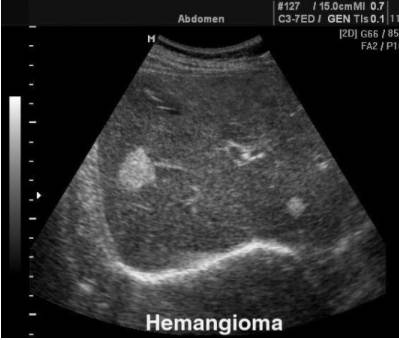

УЗИ – данный метод исследования эффективен только в том случае, когда очаговое образование располагается на передней части органа. Чем глубже место ее локализации, тем менее точным будет диагноз. Результаты УЗИ обязательно должны подтверждаться КТ или МРТ, что позволит дифференцировать опухоль от злокачественной, а также определиться с лечением.

Пока новообразование маленькое, выявить его наличие практически невозможно. Происходит это по двум причинам. Во-первых, некоторые аппараты УЗИ не способны зафиксировать новообразования менее 1 см в диаметре. Во-вторых, не проникая в саму печень, опухоль длительное время может не провоцировать никаких симптомов.

Диагностика гемангиомы печени обычно начинается с ультразвукового исследования, которое позволяет визуализировать опухоль. Для более точного определения ее размера и структуры могут использоваться компьютерная томография (КТ) или магнитно-резонансная томография (МРТ). В большинстве случаев гемангиомы не требуют биопсии, так как их доброкачественная природа может быть подтверждена с помощью визуализирующих методов.